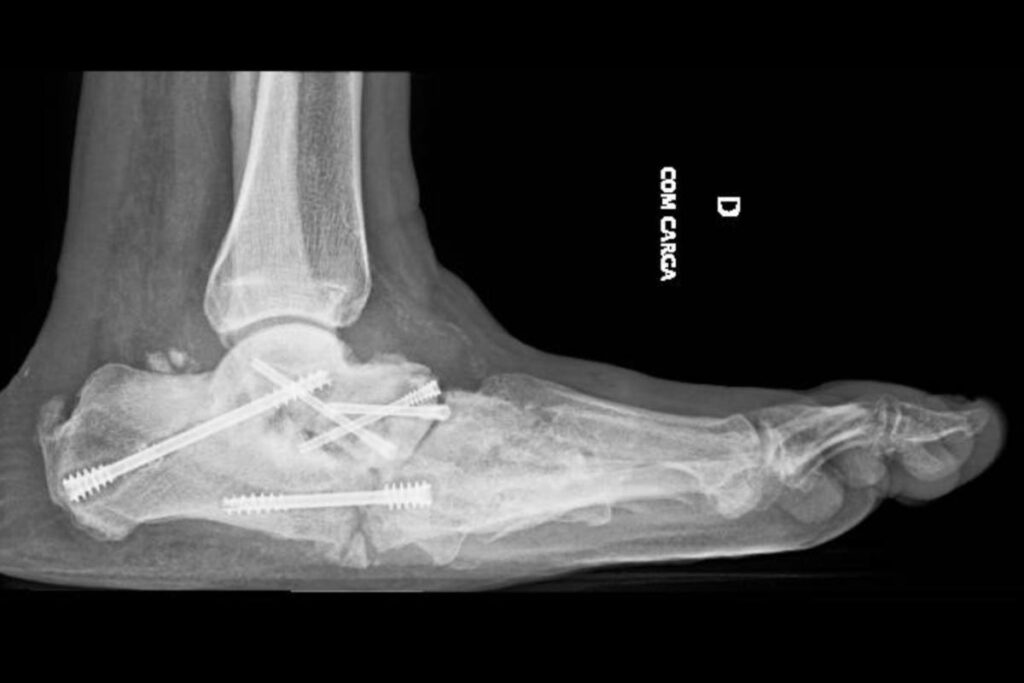

Imagens clínicas e de radiografias demonstrando um paciente com Artropatia de Charcot. Fonte: DOI: 10.1186/s13244-019-0768-9

Exemplo de artropatia de Charcot – Fraturas diversas em processo de consolidação nos óssos do médio-pé.